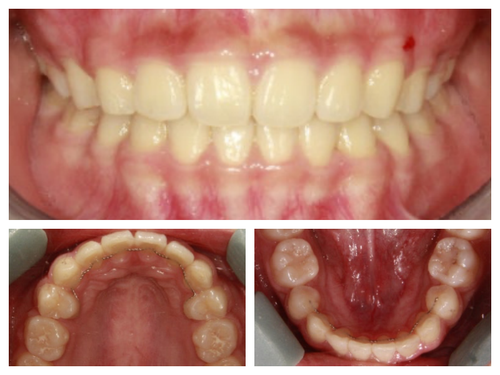

무대에 서는 친구들이라 외모에 민감하고 특히 돌출과 비대칭때문에 사진 찍을 때 신경이 많이 쓰인다고 했다.

사실 골격적인 비대칭이 심해서 교정이 끝나도 비대칭이 남겠지만 돌출이 개선되면 훨씬 예뻐질것이기에 과감히 발치를 하고 좌,우 최대한 중심선을 맞추면서 교정을 끝낸 케이스

입이 들어가서 예뻐진 것 뿐아니라 사진을 찍으면 두드러지던 비대칭도 많이 줄어들었다.

웃을때 잇몸이 많이 보이고 입이 나온것 같아 신경이 쓰인다던 발레리나

네 개의 소구치를 발치하고 교정을 시작했다.

돌출입 교정을 통해 입술의 모습이 많이 바뀌니 잇몸 노출량도 훨씬 줄어서 웃을때 신경이 더 쓰인다고...